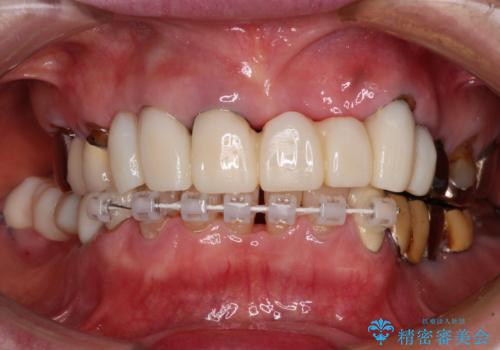

処置を予定していた歯を仮歯に変えた時点で、下顎前歯の部分矯正を行うかどうかを尋ねたところ、折角なので行いたいと言うことでしたので、矯正治療を行うこととしました。

インプラント埋入や根管治療治療など、治癒に一定の期間を要する処置の合間に矯正治療を行うことで、効率的に治療を進めて行くことができました。